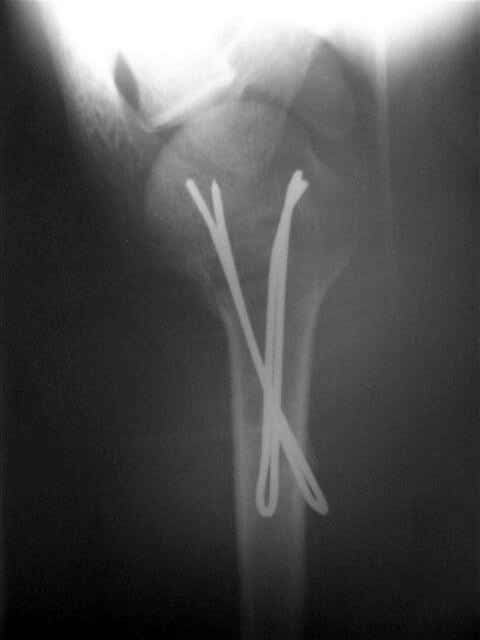

Сегодня взял больного повторно в операционную, не скажу, что повторная репозиция через неделю после первой попытки, была простая.

После удаления спиц попытался манипулировать отломками, но безуспешно, поэтому пришлось пользоваться периостальным элеватором, чтобы устранить смещение отломков и перепровести спицы. Проверил и перепроверил стабильность фиксации под ЭОПом, завтра Рг- будет готов, вот и поглядим....

Посылаю послеоперационные Рг граммы.

Всего Доброго,

Евгений И Чекашкин

Поздравляю, получилось просто замечательно. Если можно, расскажи чуть подробнее, как делали - как вправляли, как вводили спицы, поворачивали ли их?

Спасибо за поздравления:-))

Я и сам доволен результатом. В предпоследнем письме я кратко описал ход операции - закрыто репонировать не удалось( 2 недели с момента травмы и 1 неделя после неудачной репозиции) после удаления пучков спиц, пришлось сделать - 2см разрез на уровне перелома и с помощью периостального элеватора (золотое правило механики) *одеть* головку на дистальный отломок.

Спицы проводил через старые отверстия, вращая пучок импактором- направителем при его введении в головку.